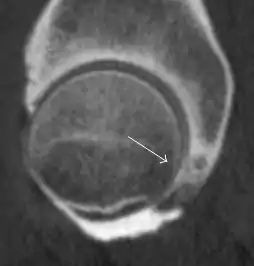

Synovial chondromatosis can be confidently diagnosed by X-ray when calcified cartilaginous chondromas are seen. However, other synovial proliferative processes, such as pigmented villonodular synovitis, require MRI for accurate diagnosis, although noncalcified synovitis can be suspected in radiographs by indirect signs, such as soft tissue swelling and/or erosions in the femoral head, femoral neck, or acetabulum (Figure 7).[1]

Figure 7:

Axial CT image of pigmented villonodular synovitis eroding the posterior cortex of the femoral neck.[1]

Sagittal T2* gradient echo image showing a posterior soft tissue mass with hypointense areas secondary to hemosiderin deposition.[1]

X-ray of synovial chondromatosis.[1]

CT of synovial chondromatosis.[1]

In synovial proliferative disorders, MRI demonstrates synovial hypertrophy. In the case of PVNS, characteristic foci of low signal intensity related to hemosiderin deposition are better seen on gradient echo T2* images (Figure 7). In the case of synovial osteochondromatosis, the synovial hypertrophy is accompanied by intermediate signal cartilaginous loose bodies and/or low signal calcified loose bodies.[1]